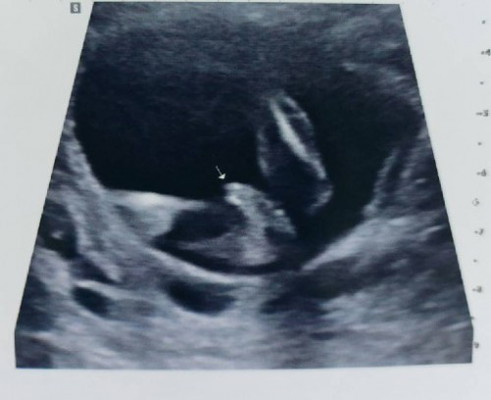

คุณหมอบอกว่า เห็นจุ้ดจู๋ น่าจะเป็นเด็ก ผช 80% อายุครรภ์ 15W ค่ะ

รูปคล้ายกับเราเลย16w คุณหมอบอกน่าจะเป็นผู้ชายค่ะ

จู๋ชัดเลยค่ะ